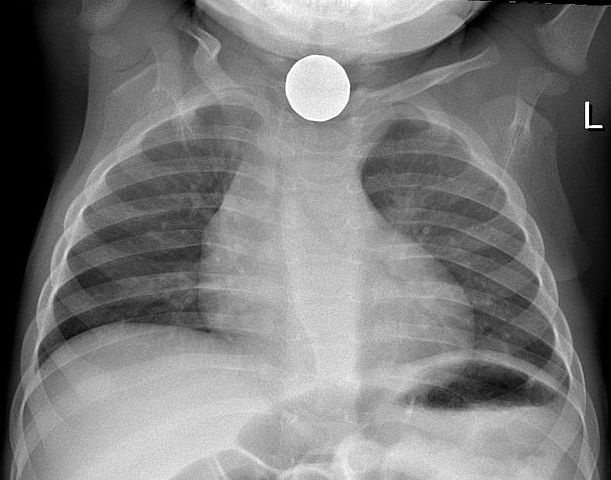

PA view Chest X-Ray of Canadian dollar coin in esophagus of child. Released per permission of mother. -- Samir धर्म 06:18, 6 June 2006 (UTC)

| current | 06:18, 6 June 2006 | 782×614 (66 KB) | Samir ( Talk | contribs) | (PA view Chest X-Ray of Canadian dollar coin in esophagus of child. Released per permission of mother. -- ~~~~) |